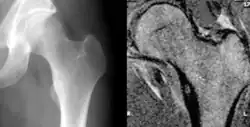

Osteoid osteoma of the lesser trochanter: X-ray and MRI with marked sclerosis around the nidus

Radiographs in osteoid osteoma typically show a round lucency, containing a dense sclerotic central nidus (the characteristic lesion in this kind of tumor) surrounded by sclerotic bone. The nidus is seldom larger than 1.5 cm.

The lesion can in most cases be detected on CT scan, bone scans and angiograms. Plain radiographs are not always diagnostic. MRI adds little to the CT findings which are useful for localisation. Radionuclide scanning shows intense uptake which is useful for localisation at surgery using a hand held detector, and for confirmation that the entire lesion has been removed.[8][9]